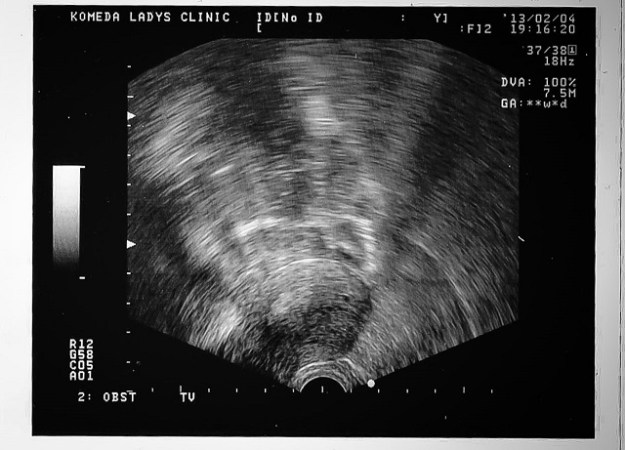

Nous arrivons dans une toute petite clinique privée, et le médecin (un grand père qui doit bien avoir 70 ans au bas mot) nous annonce que ma femme est bien enceinte. C’est le seul point positif que j’ai trouvé à cette visite qui m’a fortement déçue :

• L’échographie ne donne évidemment rien car à 4 SA (Semaine d’Aménorrhée) c’est encore beaucoup trop tôt – déception.

• L’écho nous coute ¥12.000 alors que tout le monde savait qu’elle ne donnerait rien. A ce rythme la, les coupons vont s’envoler … déception.

01 - 4sa

4sa